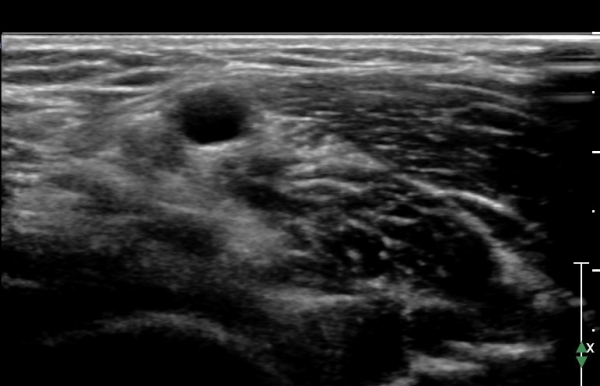

ÃÊÀ½ÆÄ °Ë»ç : ȸ³»±Ù ±ÙÀ§ºÎ¿¡¼ Á¤Á߽Űæ Ⱦ´Ü¸é°Å»ç¿¡¼ ƯÀÌ ¼Ò°ßÀ» º¸ÀÌÁö ¾ÊÀ¸³ª(»çÁø 1) ȸ³»±Ù ¿ä°ñµÎ ±â½ÃºÎ ¿¡¼ Á¤Á߽ŰæÀÇ ±¹°íÀû ¾Ð¹Ú ¹× ÆíÆòȰ¡ °üÂûµÊ(»çÁø 2). ÀÌ·± º¯È´Â °ÇÃø(»çÁø 5)°ú ºñ±³ÇÏ¸é ¶Ñ·ÇÇÔ.